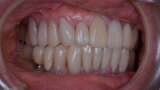

Figure 26 Closed mouth post op